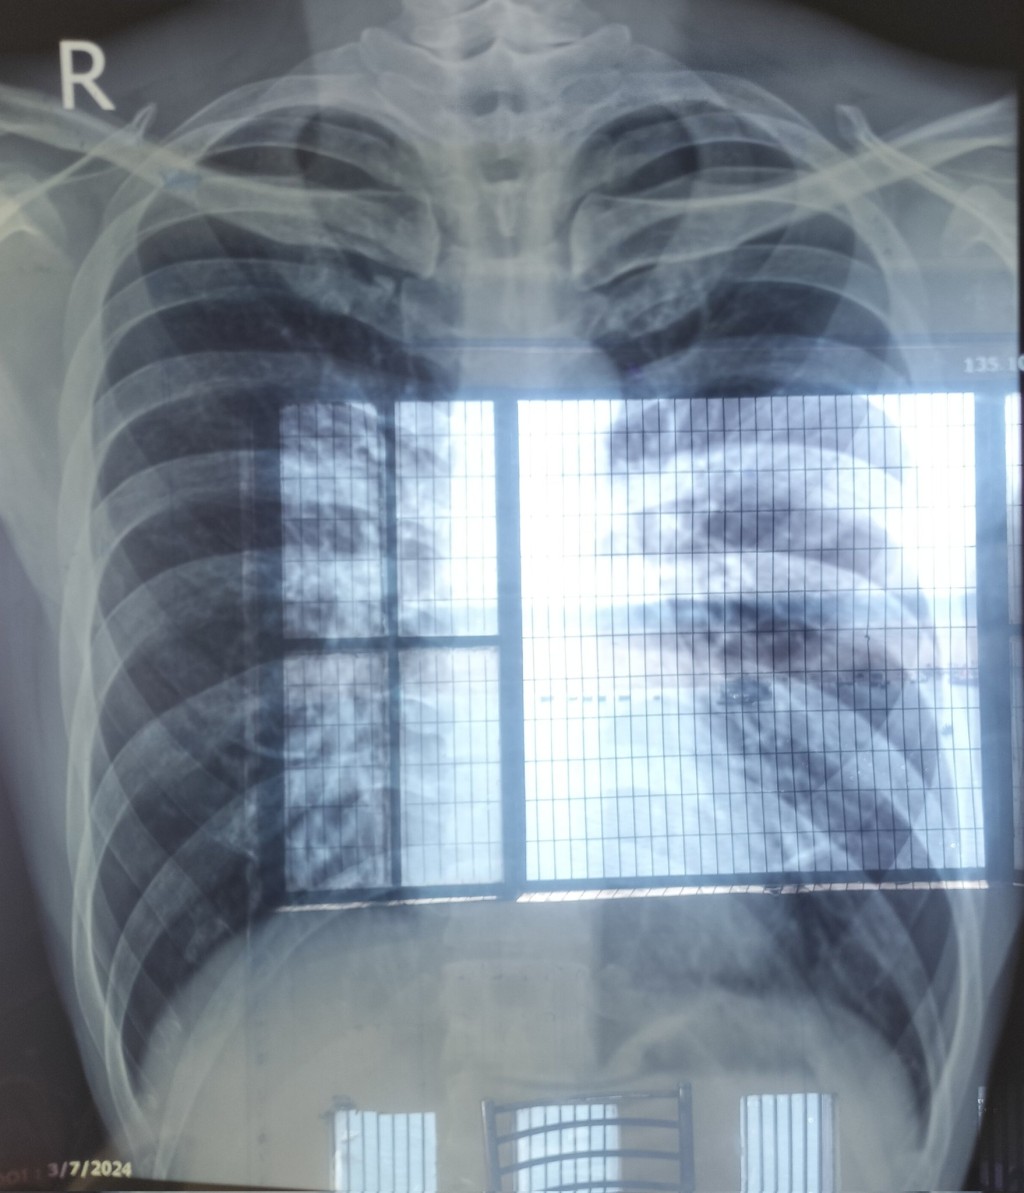

「Dotabata」事發發高燒、呼吸困難住院。 X@DorabataGG